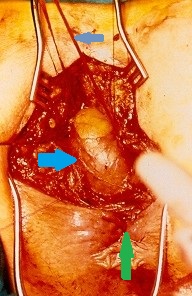

Ακραία φλεγμονή του αριστερού ημικολικού δευτεροπαθώς σε εκκολπωματίτιδα και καλυμμένες διατρήσεις (Ευγενική παραχώρηση Dr. V. Penopoulos)